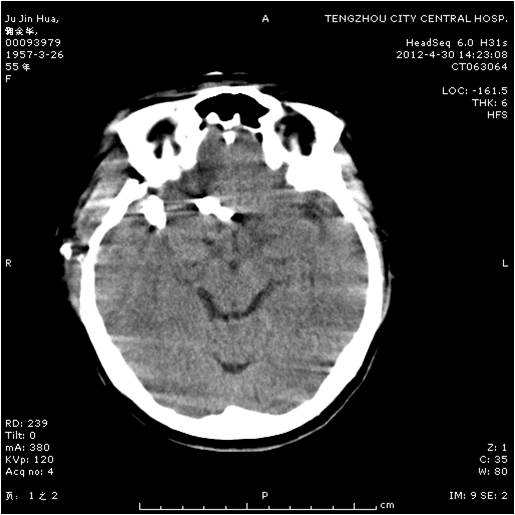

動脈瘤夾閉術前 動脈瘤夾閉術后